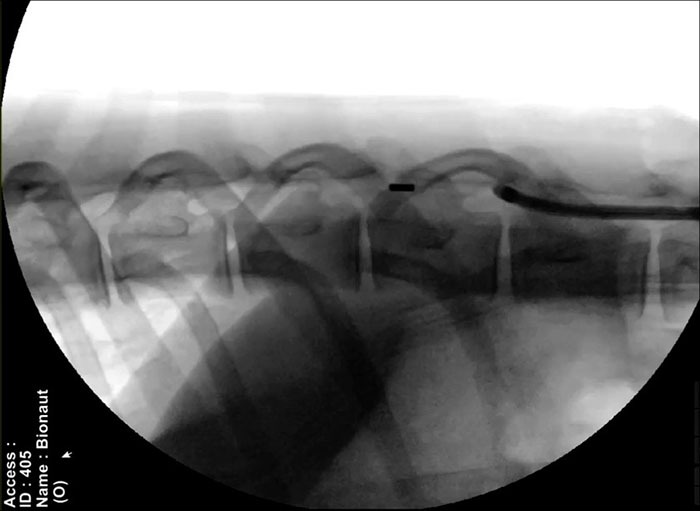

Миниатюрные винты, вращаясь, будут проходить через внутренние пространства тела, пока не достигнут цели и выпустят лекарство. Затем они вернутся к месту инъекции для удаления из организма. Медицинские работники смогут отслеживать их перемещение с помощью рентгеновских лучей и управлять ими при помощи магнитов.